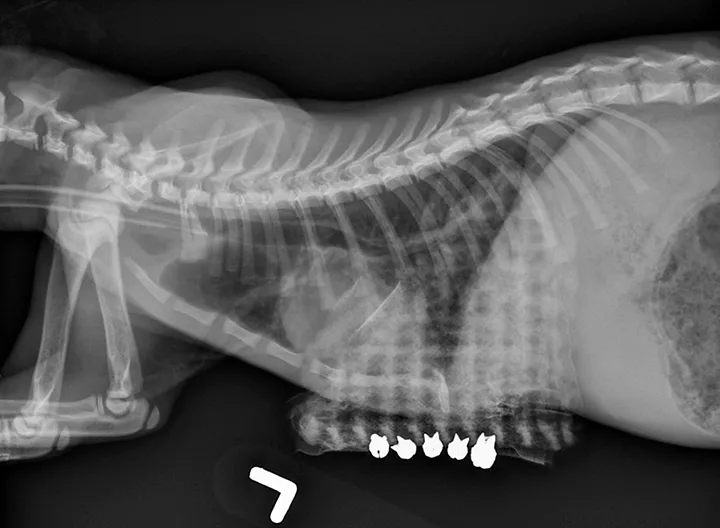

The brace should be created from a moldable (preferably radiolucent) material and should be U-shaped to fit around the ventral thorax, extending approximately three-fourths of the way to the spine. Surgical scrub sponges can be used to pad the edges of the brace to prevent pressure sores, and holes can be created along the ventrolateral aspects of the brace to allow for suture passage. Percutaneous sutures should be placed around the sternum (ie, circumsternal) and through, around, or over the brace. The sutures should be tightened and secured so the sternum is pulled outward. To allow evaluation and cleaning of the region, the sutures can be secured by tying in a bow or with replaceable split shot fishing sinkers to allow for loosening and/or retightening. After placement of the circumcostal sutures and brace, lateral radiographs should be obtained to evaluate the position of the sternebrae and verify improvement in the thoracic width as compared with pretreatment measurements (Figure 2). The brace should be kept in place for several weeks until the sternum is sufficiently stiff to prevent inward displacement.

A lateral thoracic radiograph of a cat with a radiopaque mesh-like structure overlying the caudoventral aspect.

FIGURE 2

Patient in Figure 1. The sternum has been pulled ventrally and secured by circumsternal sutures to an external brace with removable split shot fishing sinkers.